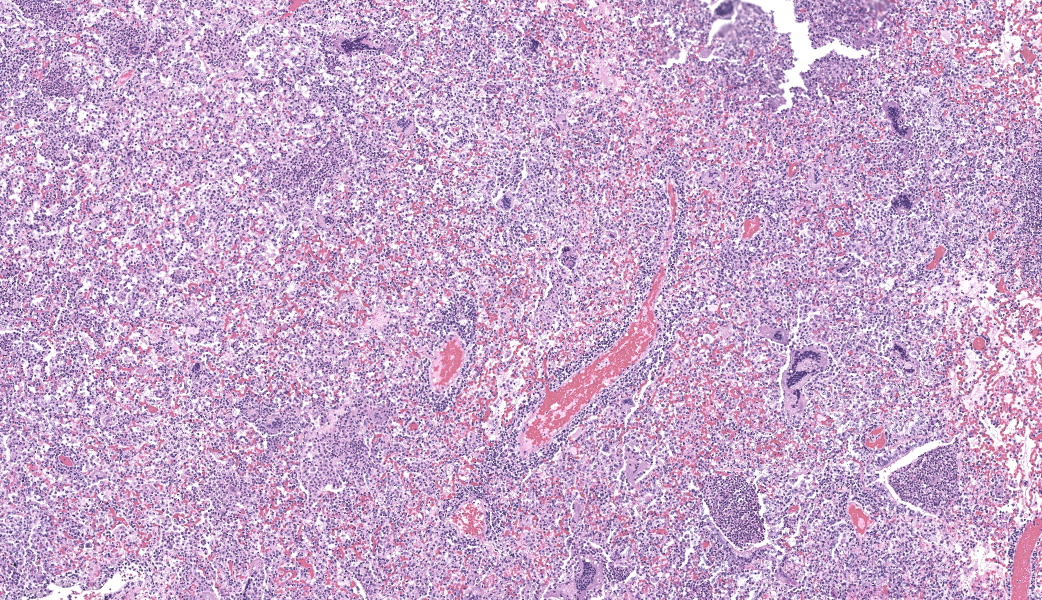

Lung, multiple sections. Within a single section of lung, approximately 75% of the bronchial, bronchiolar, and alveolar lumina contain overall large numbers of neutrophils, macrophages, large multinucleated cells, cellular debris, homogenous eosinophilic material, fibrillary eosinophilic material, and occasionally scattered erythrocytes. The multinucleated cells are often large and bizarre in appearance, some containing approximately 40 nuclei. The cytoplasm of these multinucleated cells is eosinophilic and variably granular to homogenous. A subset of these multinucleated cells contains few distinct optically clear vacuoles, while others demonstrate phagocytosis of few neutrophils. There is mild vascular congestion throughout, and there are small clusters of lymphocytes cuffing airways multifocally.Contributor's Morphologic Diagnoses:

Pneumonia, bronchoalveolar, suppurative, histiocytic, focal, subacute, severe with intraluminal multinucleated giant cells.Contributor's Comment:

Lung: Bronchopneumonia, histiocytic and neutrophilic, chronic, multifocal to coalescing, severe, with numerous multinucleated giant cells.JPC Comment:

Our fourth conference this year was moderated by the esteemed Dr. Thomas Cecere from Virgina Tech. The JPC team was thrilled to have him back for the second year in a row. This first case provided a great discussion on diagnostic workups and the processes that the pathologist should consider when choosing next steps in a case. Here, the lungs were “chock-a-block” full with histiocytic and neutrophilic inflammation with numerous giant cells that one participant remarked as having “a million nuclei.” These were some of the most impressive giant cells that many participants had seen. The bacteria were very difficult to see on the H&E, but the pattern of inflammation and presence of such robust giant cells should clue one into the presence of infectious organisms. As such, next steps should include a full gamut of routine infectious organism stains, including gram stains, acid fast stains, and fungal stains (GMS, PAS). Given that these were performed by the contributor, only confirmatory GMS and Fite-Faraco (FF) stains were performed in house, which revealed weakly acid-fast, GMS-positive organisms within multinucleated giant cells. This is consistent with the Nocardia spp. that were identified by the contributor. Those “chef’s kiss” multinucleated giant cells, though, deserve some recognition here.The multinucleated giant cell macrophage is a truly remarkable physiologic phenomenon. How they are formed is poorly understood. The current understanding is that macrophages need to be present in chronic inflammation, where they are constantly exposed to pro-inflammatory cytokines, such as IFN-γ, IL-3, IL-4, IL-13, and GM-CSF, as well as pathogen-associated molecular patterns (PAMPs) and other mediators of inflammation.1 A common setting in which these “ingredients” are found is in fungal infections or when dealing with foreign bodies, both of which can sometimes be too large for inflammatory cells to phagocytose and handle on their own. In this environment, macrophages will be in close association with one another and will begin to express molecules on their cell surface that enable fusion with one another, including dendritic cell-specific transmembrane protein (DC-STAMP; major driver of fusion), β1 and β2 integrins, CD44 (hyaluronic acid receptor), CD47 (integrin-associated protein), macrophage fusion protein receptor (MFPR), fusion regulatory protein (FRP-1, also known as CD98), and P2X7 (an ATP-activated ion channel that results in pore formation).1